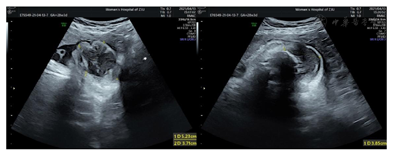

辅助检查:1.本院产前诊断超声检查示:胎位:ROA胎心:147次/分胎动:可及双顶径9.2 cm,头围32.5 cm,股骨长7.2 cm,腹围34.3 cm,胎盘:前壁GrII级,羊水指数:9.0 cm,脐动脉S/D比值2.5。备注:胎儿右侧颜面部见5.2 cm×3.9 cm×3.7 cm不均低回声,局部边界不清,内见丰富血流信号,RI:0.59;右侧上颌骨回声不规则、见回声中断,低回声与该侧上颌骨关系密切;右侧上牙槽处回声不规则、见回声中断;颈部见"U"形切迹(图1,图2,图3,图4)。诊断结果:宫内孕,单活胎,胎儿右侧颜面部不均低回声(肿瘤考虑,恶性可能),目前胎儿脐带绕颈1周。

阴道分娩一死胎,体重3240 g,Apgar评分1分钟0分,Apgar评分5分钟0分。死胎检查见新生儿全身散在蜕皮,右脸颊见一6 cm×5 cm肿块,累及右侧鼻翼。予送小尸体病检。

尸检结果:死胎,右脸颊软组织肿瘤(首先考虑为胎儿型横纹肌瘤),余体表及内脏未见明显畸形。